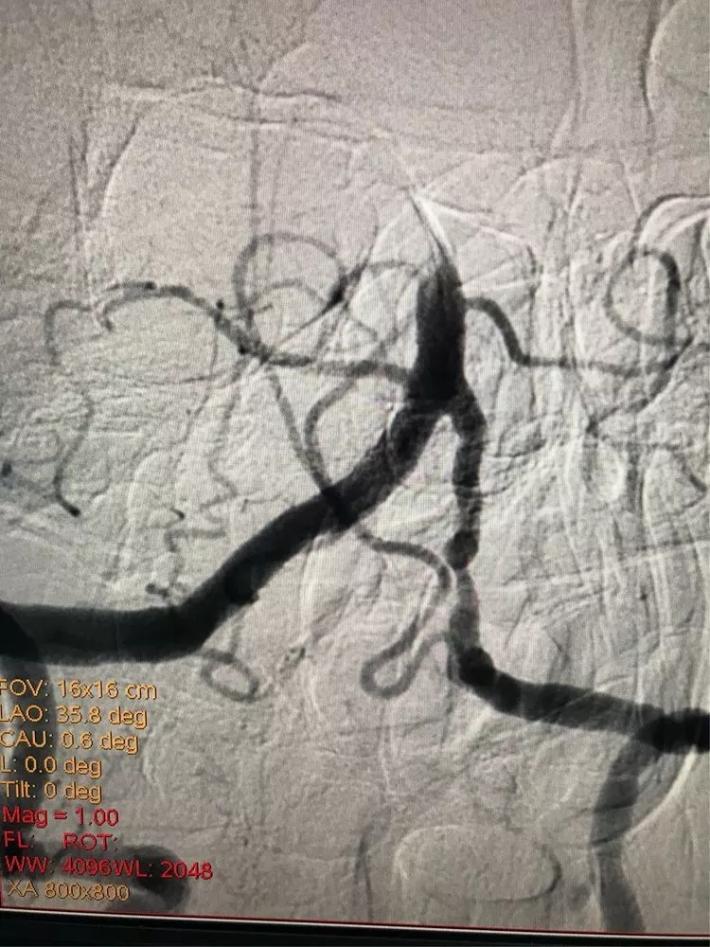

脑血管造影显示:右侧大脑中动脉闭塞。

手术步骤

微导管进入大脑中动脉远端真腔。

置入支架,见大脑中动脉有血流。

取出支架,血管未开通。

再次上微导管。

微导管进入大脑中动脉远端真腔。

第二次置入支架取栓。

血管仍未开通。

第三次上微导管。

再次置入支架取栓。

见血管再通。

支架和取出来的血栓。